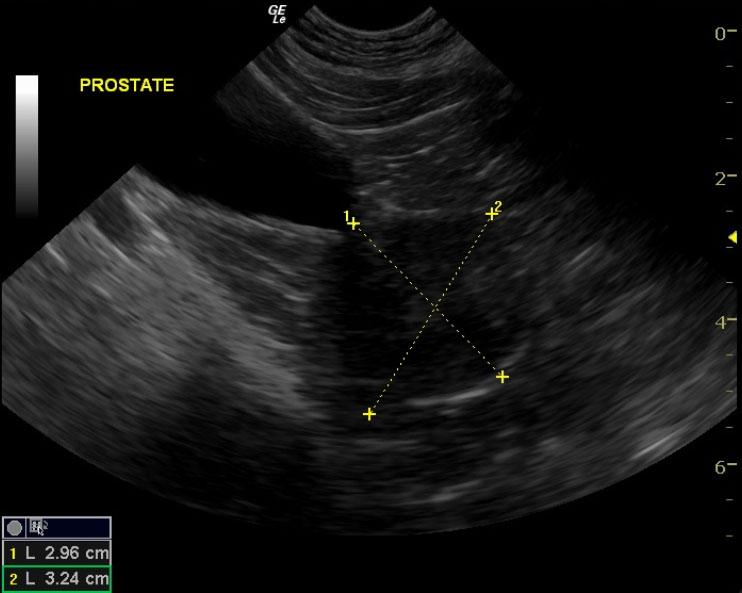

The prostate in this patient was 3.24 x 2.9 cm. It was very hypoechoic to the surrounding fat. Given the neutered male status it is strongly suggestive of prostatic neoplasia. However, this does appear uniform. Chronic prostatitis is a possibility, but less likely. Focal areas of mineralization were noted.